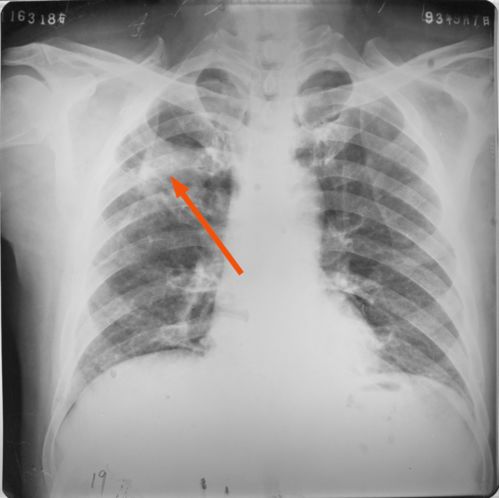

我们先来看看影像学筛查的进化。数字化胸片(DigitalRadiography,DR)早已普及,但真正的革命发生在它与计算机辅助诊断系统(CAD)深度融合的那一刻。在过去,一位经验丰富的放射科医生在疲劳状态下,可能会漏掉一个极其隐蔽的微小病灶或肺纹理的异常改变。

这种“视觉疲劳”是人类生理的局限,无法苛求。基于深度学习算法的AI诊断系统却是个“永动机”。这些系统通过成千上万份标准的结核病胸片影像进行训练,已经具备了超📘越常规肉眼的敏锐度。当一张数字化胸片被上传到系统后,AI会在几秒钟内完成全肺扫描,精准识别出浸润、增殖、干酪性病变甚至微小的空洞。

它不仅能指出疑似病灶的位置,还能给出客观的评分,这对于在偏远地区、基层医疗机构工作的医生来说,无异于请到了一位24小时在线的国家级专家。